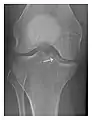

Figure 1: A 56-year-old woman presenting with left knee pain after a fall. (a) Initial anteroposterior radiograph was considered normal, however, subtle cortical disruption of the anterior rim of the medial tibial plateau, medial to the tibial spine, is noted (arrow). (b) Coronal T1-weighted MRI confirms the cortical disruption (arrow) and shows extensive fracture through the proximal tibia. (c) Coronal proton density-weighted image with fat saturation shows extensive edema in the subchondral bone. Note also hypersignal adjacent to the medial collateral ligament corresponding to a grade I sprain (arrowheads).[1]